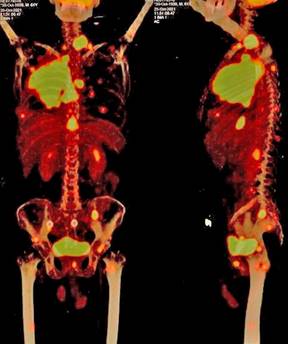

Se trata de paciente masculino de 62 años que presentó dolor cervical y lumbar, una tomografía computarizada reveló una masa en el lóbulo superior del pulmón derecho. La biopsia diagnosticó adenocarcinoma infiltrante pobremente diferenciado, y la tomografía por emisión de positrones con tomografía multicorte (PET/CT) mostró metástasis en el canal raquídeo C7/T1, adenopatías mediastinales, lesión esofágica y múltiples lesiones osteolíticas (Figura 1). La secuenciación de nueva generación reveló mutaciones en EGFR (L861Q) y TP53 (ss672+1G>T), así como amplificación EGFR, MET, BCL2L2 y NKX2-1.